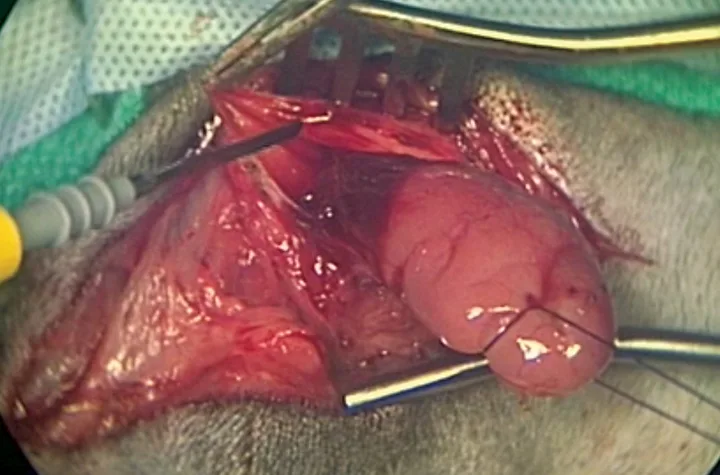

Insert hemostatic forceps from cranial to caudal under the digastricus muscle to grasp the gland/duct complex (A). Exercise caution to limit connective tissue being entrapped in the jaws of the forceps. Amputate the gland/duct caudal to the hemostatic forceps, and use the forceps to retract the gland/duct craniomedially under the digastricus muscle. Identify the lingual nerve, and dissect and ligate the duct at the level of this nerve (B). Excise the remaining sublingual salivary tissue/duct and submit for pathology.